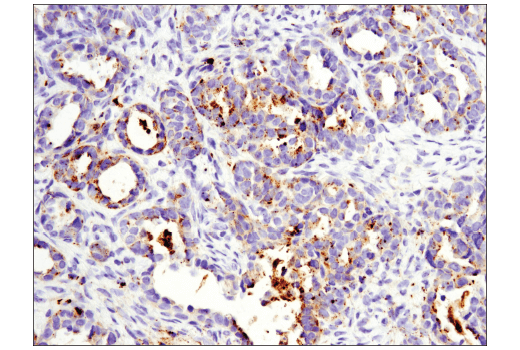

OX40L (D6K7R) Rabbit Monoclonal Antibody #59036

• IHC

IHC Leica Bond 1:200

Immunohistochemistry (Paraffin) 1:200

OX40L (D6K7R) Rabbit Monoclonal Antibody recognizes endogenous levels of total OX40L protein. Staining of unknown specificity has been observed in skeletal muscle.